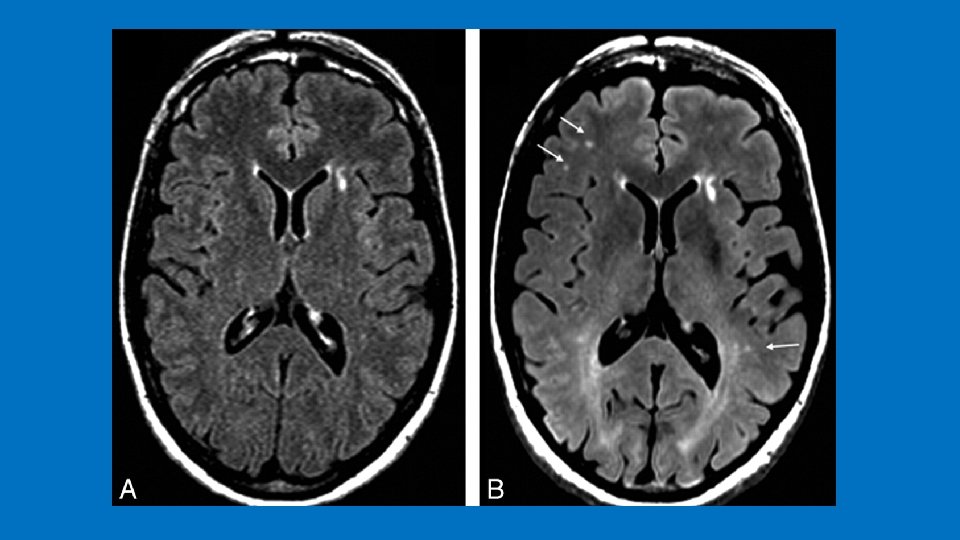

Hydrocaphalus